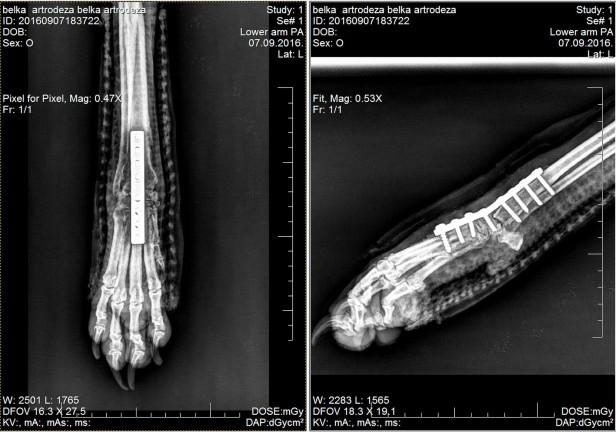

"Jedino rešenje da prohoda bila je operacija. Veterinar je operisao Beliku 2. avgusta i tada su joj u desnu nogu ugradili pločicu. Deset dana bila je u stacionaru, gde su je previjali i gde je primala terapiju", objašnjava Pavlovićeva.